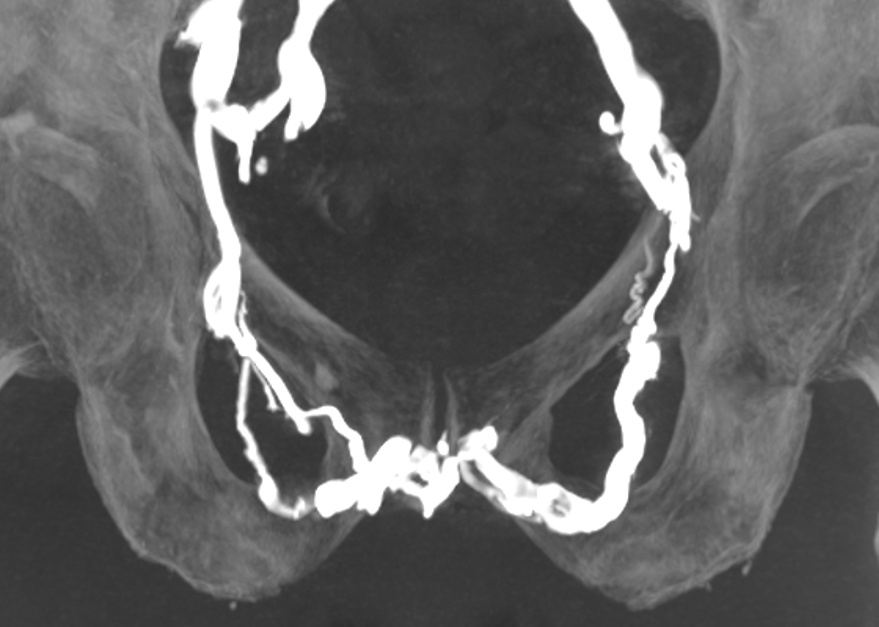

Pathologies urologiques et gynécologiques :

- Myomes utérins et adénomyose, varices pelviennes, varicocèles, endométriose pariétale, dysfonction érectile, hypertrophie de prostate

Lésions vasculaires :

- Artères : artériopathie oblitérante, pied diabétique,

- Veines : thrombo-aspiration de phlébite récente ou embolie pulmonaire, recanalisation de séquelles de phlébite, syndrome de Nutcracker, syndrome de May-Thurner/Cockett